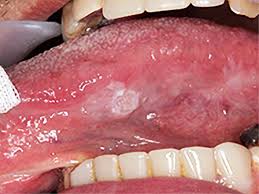

① 0기 (상피내암, Carcinoma in situ)

- 특징: 암세포가 점막의 가장 바깥층에만 존재하며, 주변 조직으로 침범하지 않은 상태입니다.

- 증상: 대부분 무증상이나, 입안에 붉거나 하얀 반점이 나타날 수 있습니다.